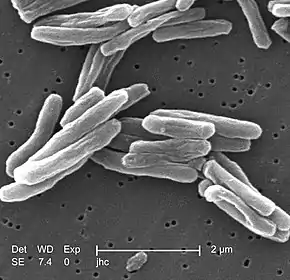

Jacek Tomczyk and a team from Poland and the United Kingdom have examined a 30 – 34-year-old female from Tell Masaikh in Syria and attempted to differentially diagnose multiple pathological conditions observed on the bones. Morphological, histological, radiological and molecular methods were applied in order to assess the pathological lesions. This led to the identification of some possible pathological conditions linked with the changes seen on the bones. Mycobacterium tuberculosis (MTB) and serious traumatic changes subsequent to a secondary infection were narrowed down in the differential diagnosis; however, MTB was not detected in the molecular analysis (ancient DNA). The authors stressed the complications associated with differentially diagnosing pathological conditions from ancient skeletal remains.